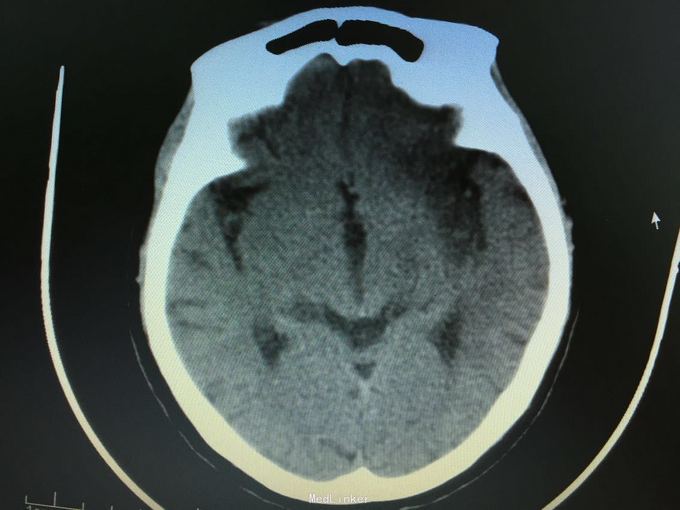

主诉:突发左侧肢体无力伴意识障碍2.5小时。 现病史:患者于2.5小时前突发左侧肢体无力,左侧肢体完全不能动,伴有意识障碍,急诊头CT显示多发脑梗死,为进一步诊治入院。 既往史:高血压,冠心病支架后,阵发房颤。

昏睡,完全混合性失语,双眼向左侧凝视,右侧肢体肌力0级,右侧病理征阳性。 头CT见多发陈旧小梗死。

目前住院10余天,意识清楚,但仍遗留左侧肢体肌力0级,混合性失语等严重功能残疾。复查CT显示为左侧大脑半球大面积脑梗死。 讨论:对于高龄,大面积脑梗死患者,时间窗内是否溶栓?静脉还是动脉溶栓?